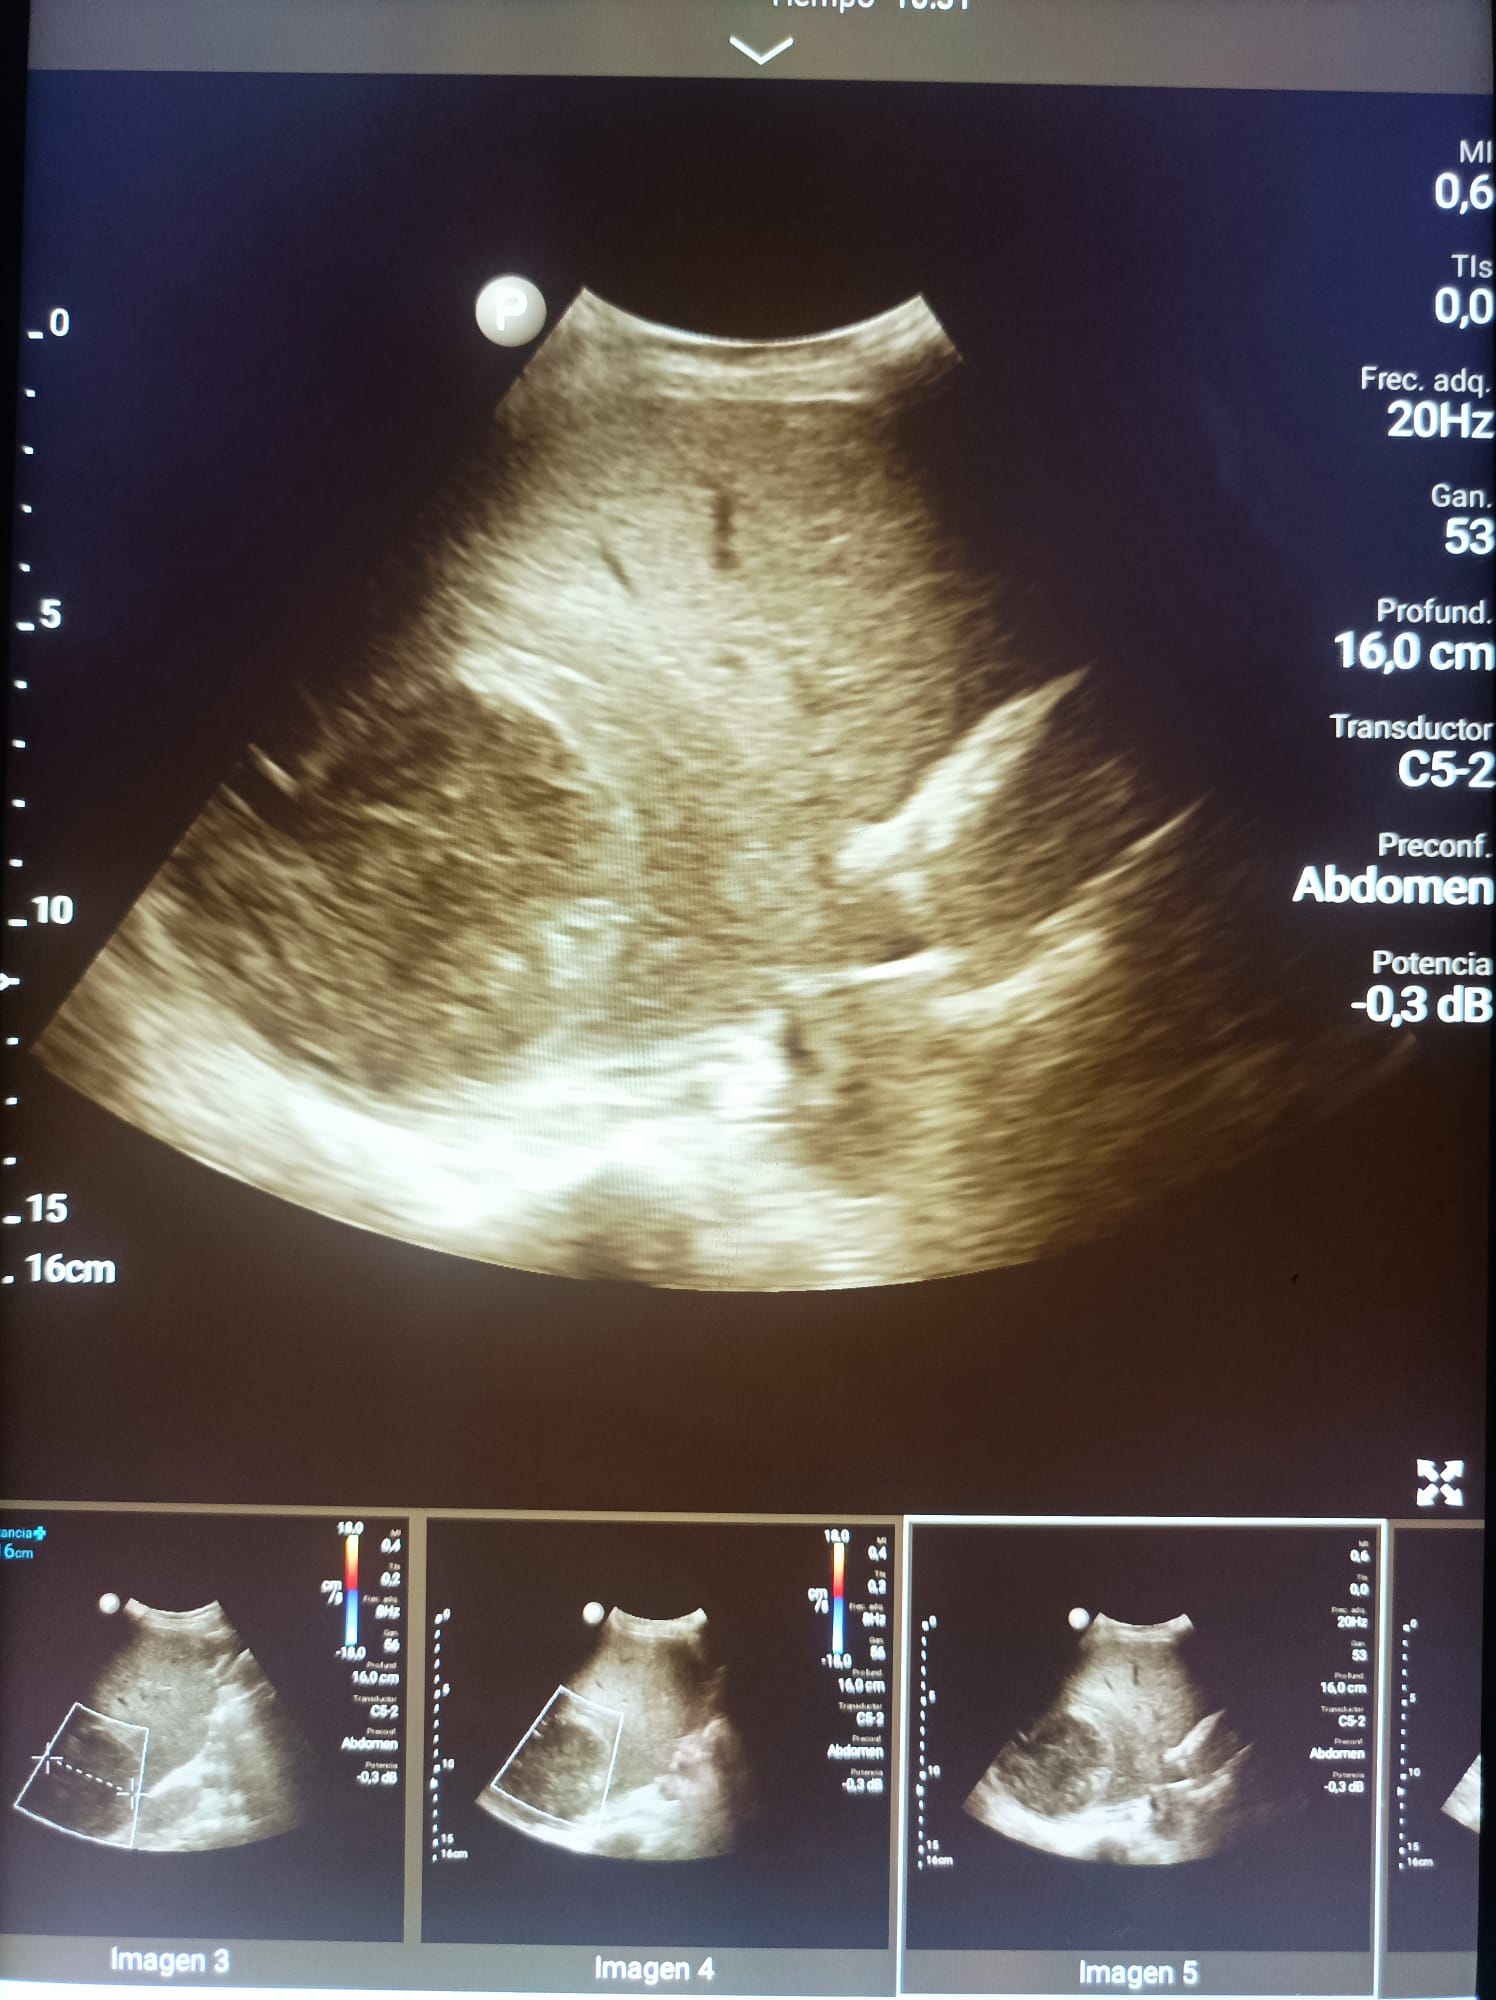

Disponíamos de una sonda convexa que nos ha permitido la realización de ecografías abdominales, pulmonares e incluso obstétricas en diferentes ámbitos; servicio de urgencias, servicio de cirugía general y medicina interna.

Las patologías mas prevalentes han sido la ascitis y la insuficiencia cardiaca, asi como pacientes politraumatizados que se han beneficiado de FAST a su entrada en urgencias.

Otras patologías diagnosticadas han sido: abscesos hepáticos, derrames pleurales, tumores hepáticos, abortos espontáneos e incluso miocardiopatía hipertrófica.

Además de diagnósticos, hemos podido realizar ciertas técnicas invasivas como paracentesis e incluso toracocentesis eco guiadas, disminuyendo asi las complicaciones secundarias a las mismas.